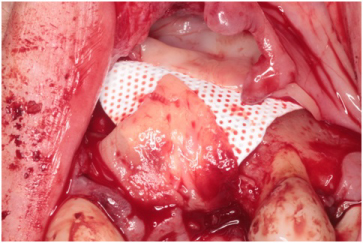

The patient received 2 gm of amoxicillin as an antibiotic prophylaxis (Zimox, Pfizer Inc., USA). Intravenous sedation was administered and approximately 30 cc of venous blood was drawn in order to prepare 3-5 cc of platelet rich fibrin (PRF). 2% Lidocaine HCL 1:100, 000 with epinephrine (Septodont Cook-Waite, Lancaster, PA, USA) was used for local infiltration at the #s 6-11 sites. Both surgical sites were prepared in the same manner. Bilateral papilla sparing incisions were completed (Figure 4 and Figure 5). Once the labial or buccal aspects were exposed, a #7011 bur was used to perforate the bone and establish bleeding bone (Figure 6 and Figure 7). At both sites, a Cytoplast® Ti-250 (Osteogenics Biomedical, Lubbock, TX, USA) titanium reinforced membrane shaped and sized to cover the proposed GBR sites and allow space for the bone regeneration to occur. The membrane each were secured with bone tacks first at the vestibule (Tru Tack® ACE Boston, MA, USA) (Figure 8). Then MinerOss® bone graft (Biohorizons, Birmingham, AL, USA) was placed at both surgical sites (Figures 9 and Figure 10) followed by a single superior membrane bone tack (Figures 11 and Figure 12). PRF was placed over the membranes (Figures 13 and Figure 14) and the surgical flaps were repositioned without tension with Cytoplast® and chromic sutures (Figures 15 and Figure 16).

Figure 13: Platelet rich fibrin placed over the membrane. View Figure 13

Figure 14: Platelet rich fibrin placed over membrane. View Figure 14